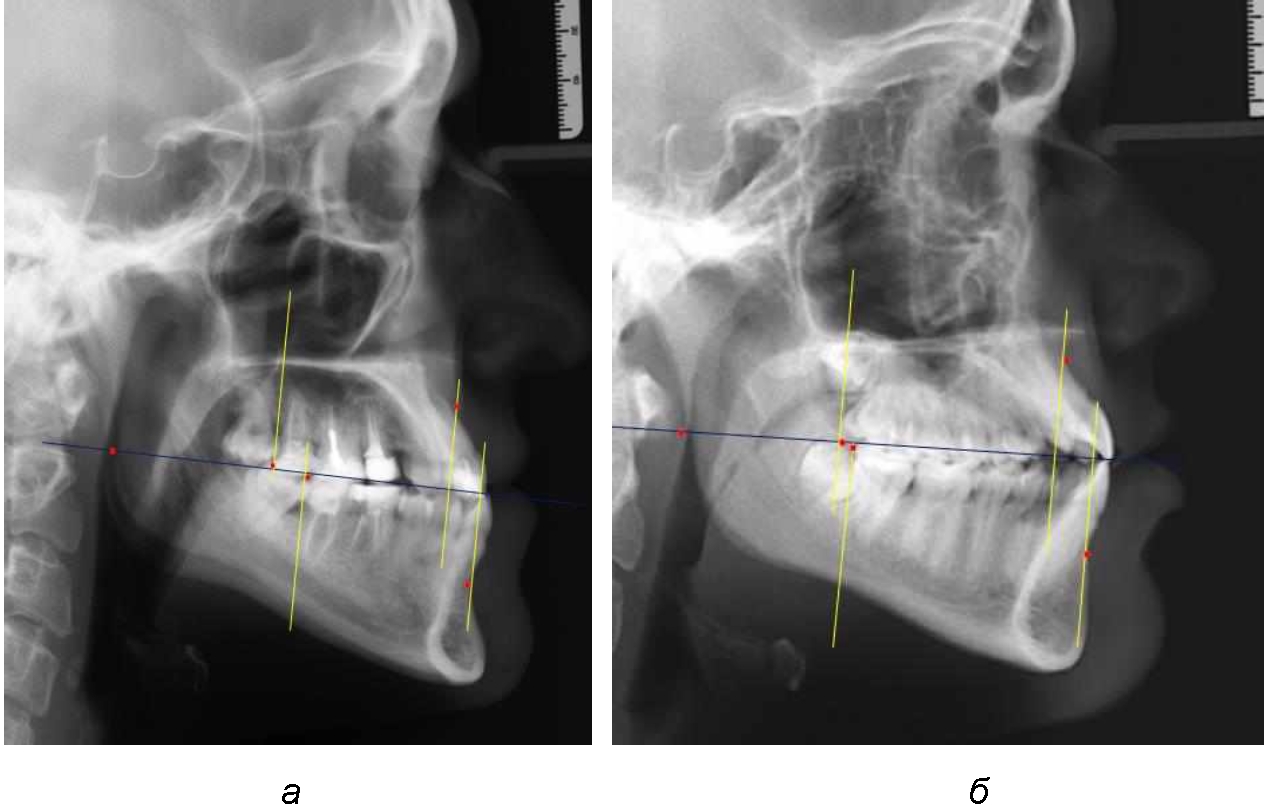

На рентгенограммах устанавливали точки Downs. На верхней челюсти субспинальная точка A(SS) располагалась в наиболее вогнутой точке альвеолярного отростка по переднему его краю. На нижней челюсти супраментальная точка B(SM) соответствовала месту наибольшей вогнутости переднего края альвеолярной части. Окклюзионную линию проводили через контактную точку резцов (vРOcP) и дистальную точку окклюзии второго нижнего моляра (hРOcP). Место пересечения окклюзионной линии с дистальным краем ветви нижней челюсти (ramus mandibule) обозначали как «rmРOcP». Перпендикулярно к окклюзионной плоскости проводили линии из точек «А(SS)» и «В(SМ)», что определяло их проекцию на окклюзионную линию. Аналогично отмечали положения дистальных окклюзионных точек верхней и нижней челюсти (рис. 1).

Рис. 1. Положение основных точек (а) и линейных ориентиров (б) для анализа положения и размеров челюстей

Альвеолярно-дентальный размер верхней челюсти и нижней челюсти оценивали по окклюзионной линии между вертикалями, ограничивающими исследуемые челюсти. Положение верхней челюсти оценивали по величине размера «rmOcP-А», а нижней челюсти по расстоянию «rmOcP-В». Линия смыкания губ обозначалась как точка «sto», вблизи которой проходила окклюзионная линия. Данный ориентир позволял провести окклюзионную плоскость при аномалиях положения резцов в вертикальном направлении, когда была сложность определения резцовой окклюзионной точки (vРOcP).